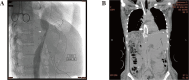

Stenosis of outflow of liver graft and migrated intracardial inferior vena cava stents Fig. 1A: Stenosis at the anastomosis of inferior vena caca and hepatic vein of the liver graft (arrow) was diagnosed 13 days post-living donor liver transplantation. Fig. 1B: Both stents stayed at their final position at the junction of the right antrum and superior vena cava (arrow).

Fig. 2

The two migrated inferior vena caca Wallstents in the right atrium were removed 40 days after their migration.